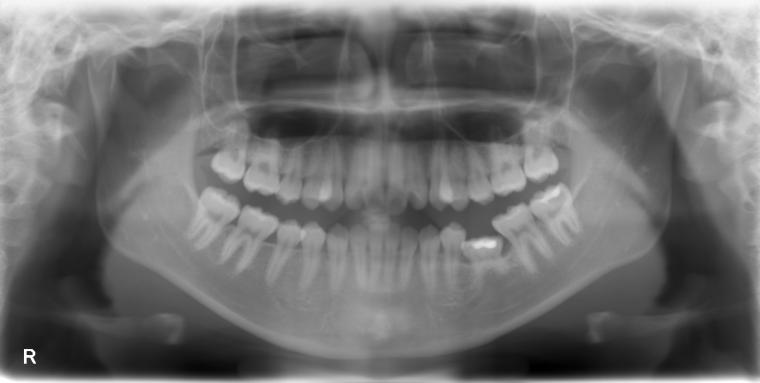

BEFORE

下顎第二小臼歯が先天性の欠損の患者さんです。

乳歯が生えていましたが、状態が悪くなり抜歯となりました。

他の歯の健康を考えマウスピース矯正で歯列を整えてからインプラントを1本埋込しました。